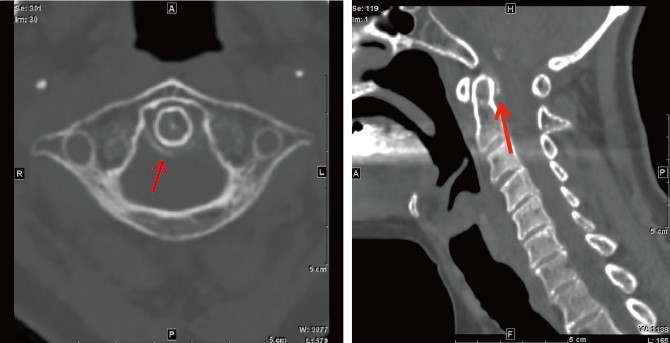

Crowned dens syndrome と石灰沈着性頸長筋腱炎。

crowned dens症候群の画像診断!まるで王冠。